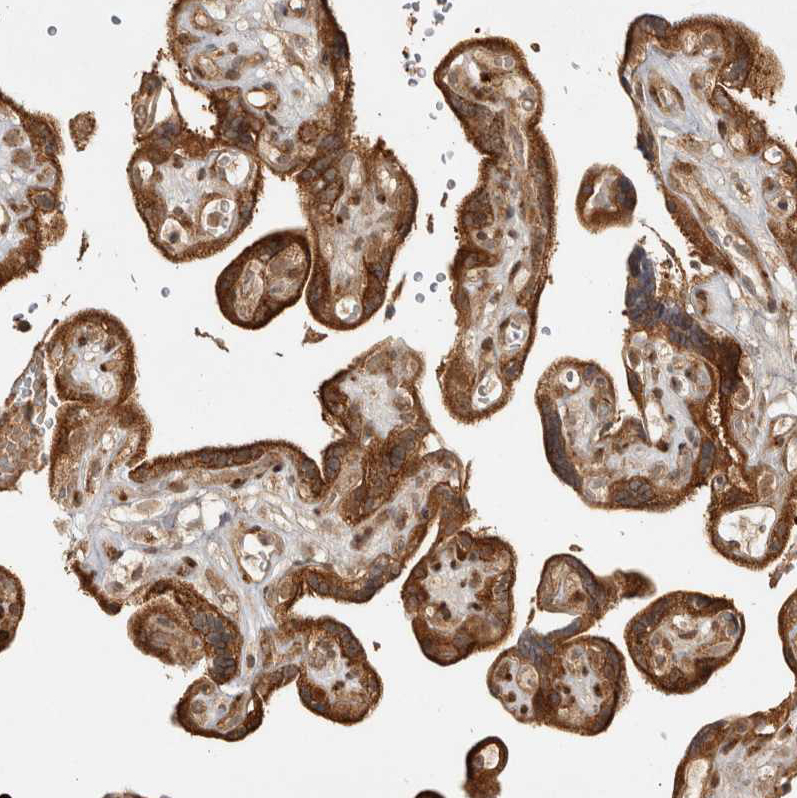

Immunohistochemical staining of human cerebral cortex, placenta, prostate and testis using Anti-CAMSAP2 antibody HPA026304 (A) shows similar protein distribution across tissues to independent antibody HPA026511 (B).